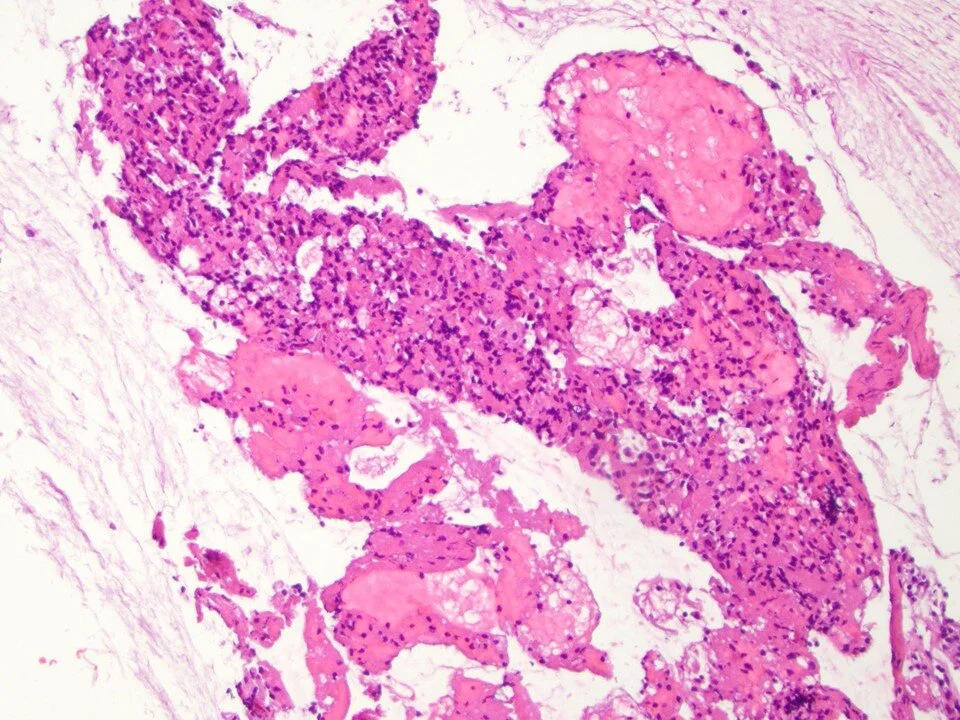

Sclerosing pneumocytoma

Sclerosing pneumocytoma - cell block